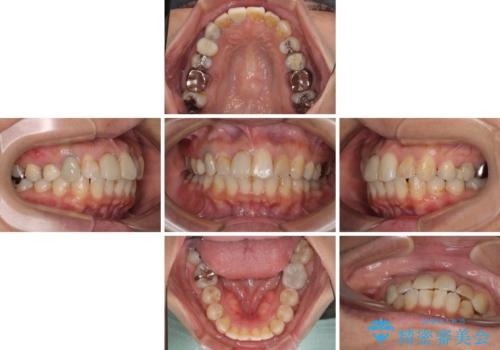

【モニター】処置歯の多い歯列 インビザラインでデコボコを整える

- 上下前歯のデコボコを気にして来院された患者様です。

歯列としては、ワイヤー装置でもインビザラインでも、どちらでも対応可能でしたが、処置されている歯が多く、ワイヤー装置を装着するためには処置歯のやり直しが必要な状態でした。

インビザラインでもアタッチメントを装着できないという同様のデメリットがありますが、比較的矯正治療を行いやすい歯列であったので、インビザラインによる矯正治療を行うこととしました。